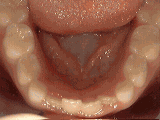

Crowding of the teeth

Patient started treatment at age eleven and wore braces for twenty-six months. He loves his new smile.